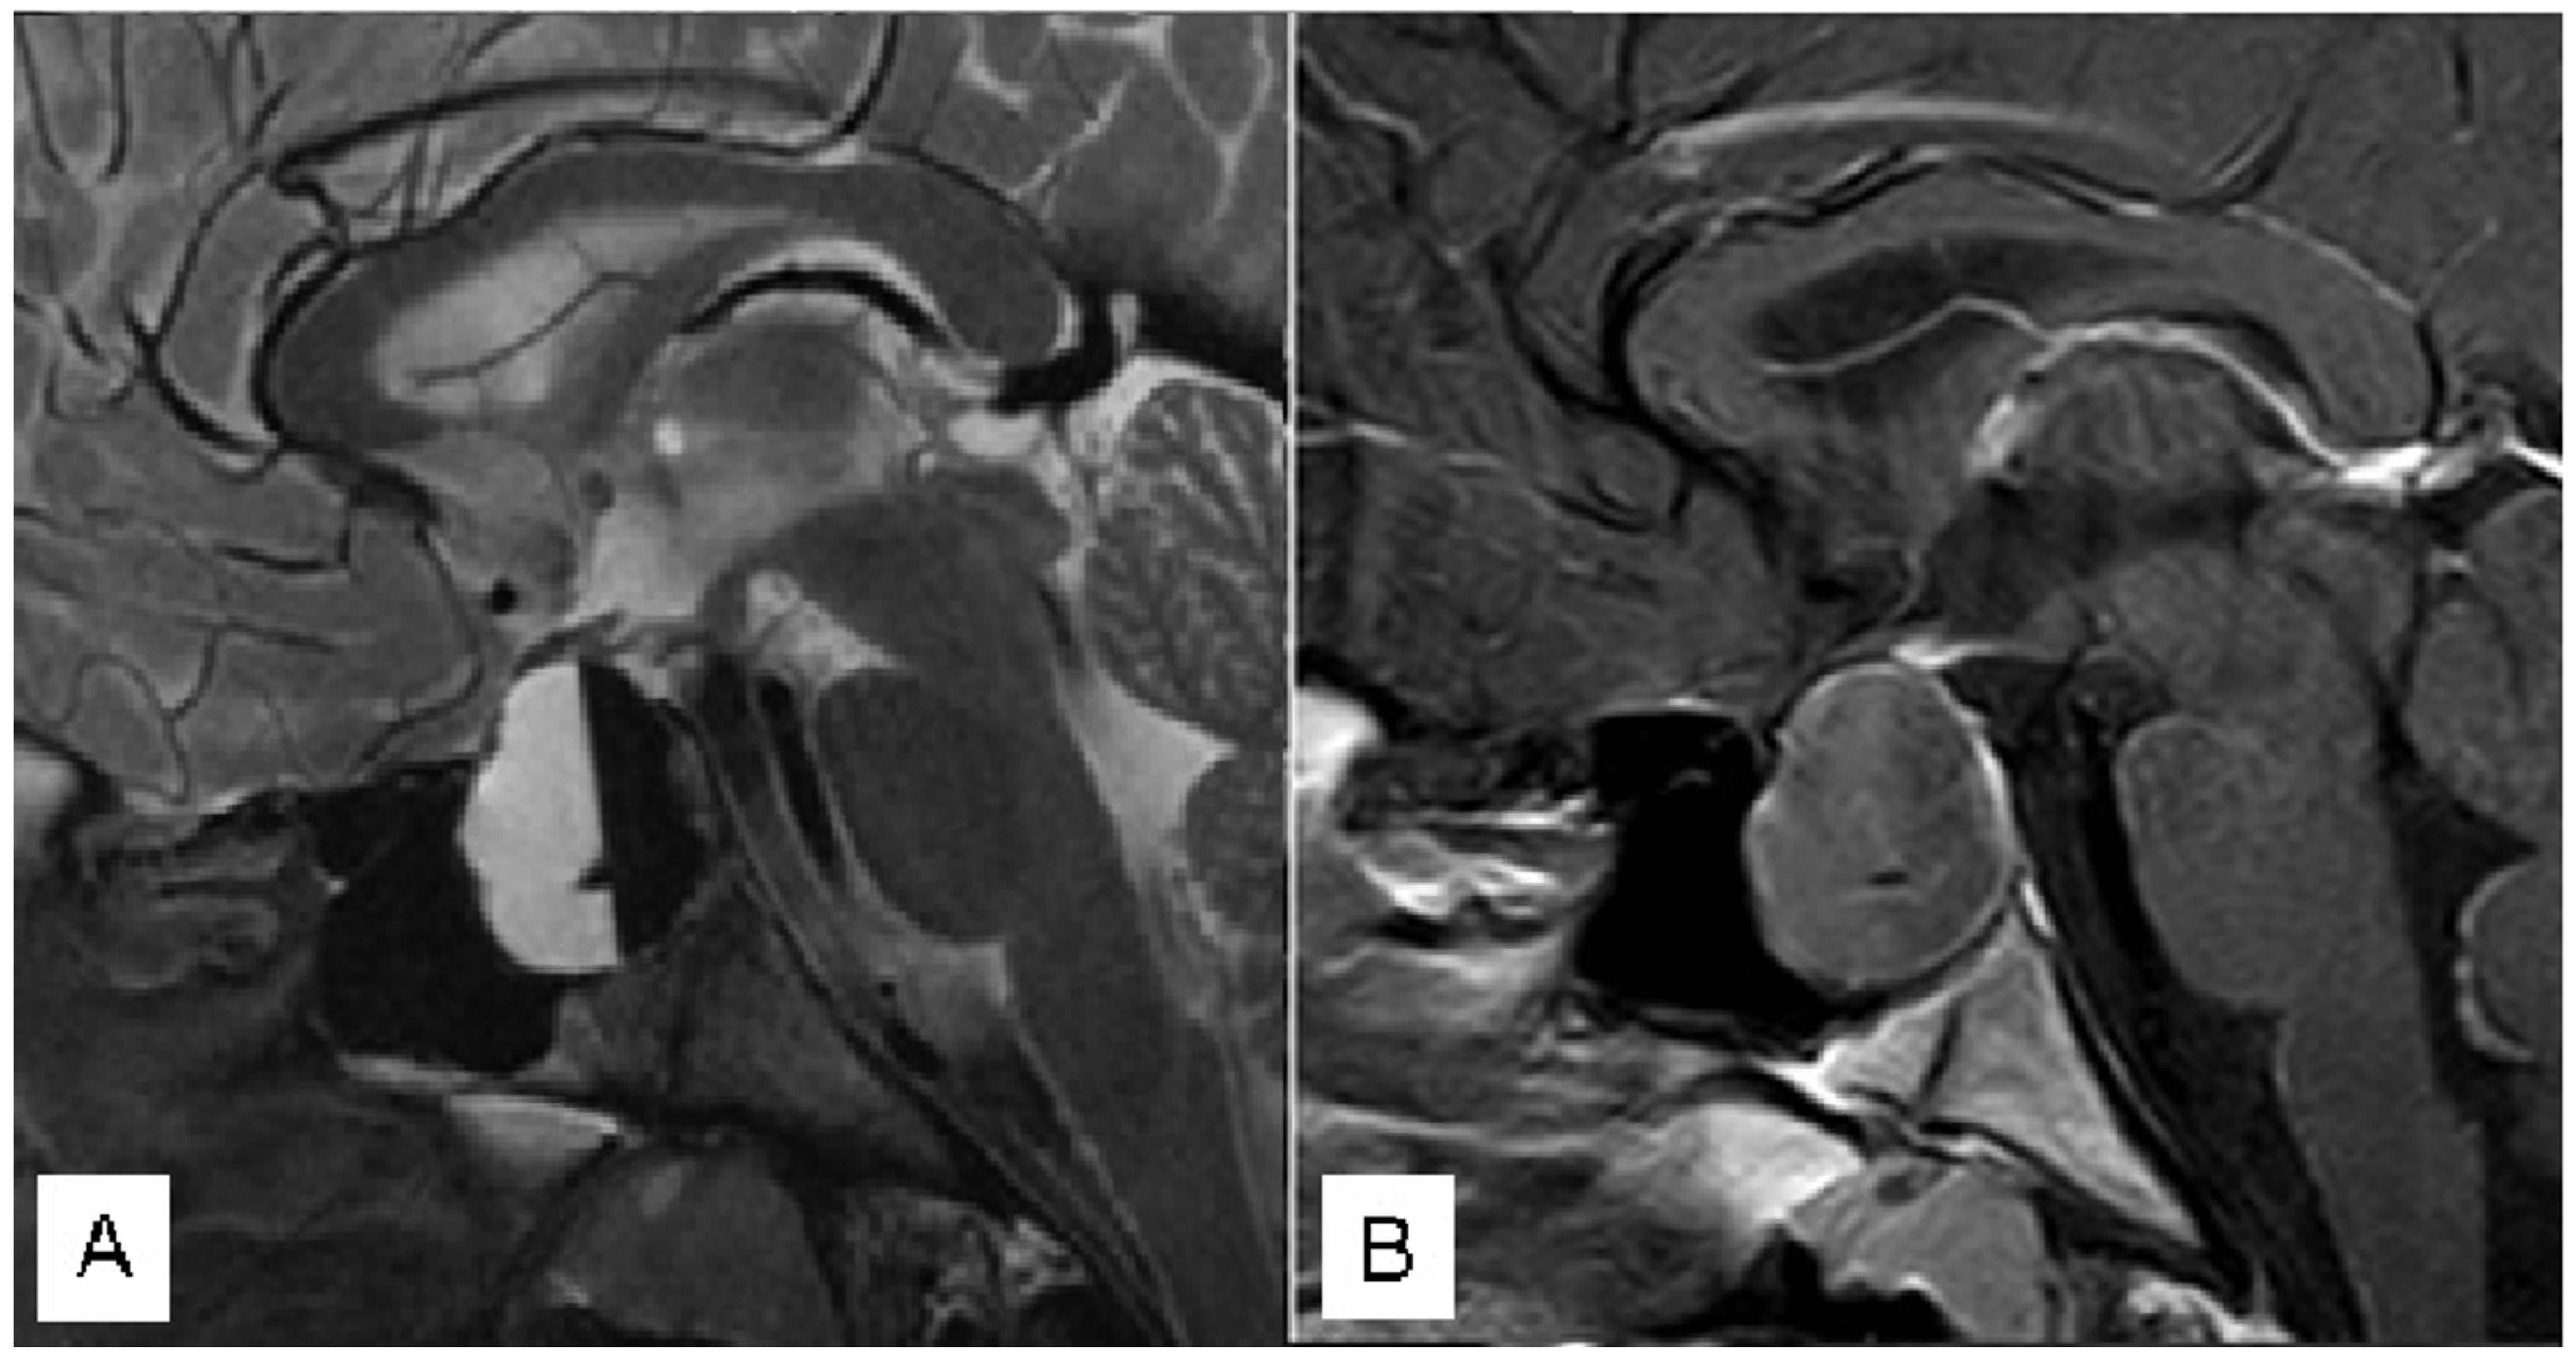

3.1.3. Case 3